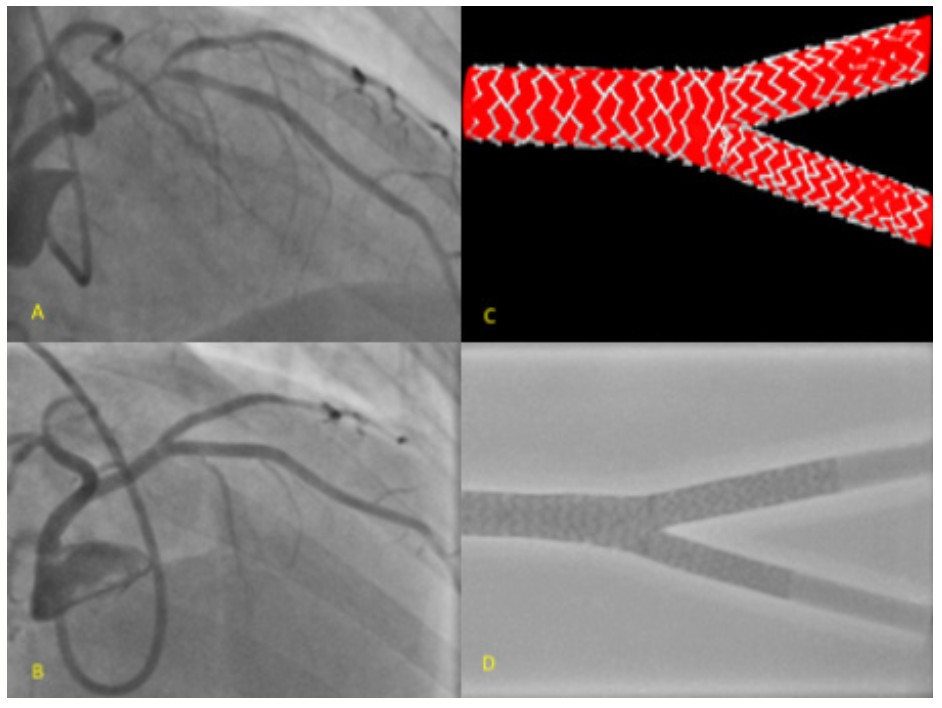

Y-stenting, also called the “skirt” technique, was initially described using a distal to proximal approach.8 It was revised by Helqvist et al in 2006,9 who reported a series of 30 bifurcation lesions treated in a proximal to distal (PD) sequence, which improved the coverage of the carina (Figure 1). The technique described herein has been further modified to be undertaken via the radial artery using a 6-Fr guide catheter, and with the option of a provisional Y-stent approach (Figure 1B). The steps of this technique are outlined as follows:

b. Medina 1,1,0 or 1,0,1. A stent with its diameter and length matched to the downstream MV/SB vessel and disease is positioned with its proximal edge abutting the upstream MV stent, and a noncompliant balloon is positioned in the SB or distal MV (Figure 6). Image-enhancement software, such as CLEARstent (Siemens) or StentBoost (Philips), is useful for ensuring exact positioning of the stent. The stent is deployed, the delivery balloon is withdrawn 1-2 mm, and kissing-balloon inflation is performed.

c. Medina 1,1,1. Two appropriately sized stents can be positioned in the downstream MV and SB, respectively, and deployed simultaneously (Figure 7). Both stent delivery balloons are then withdrawn 1-2 mm and postdilation is performed (Figure 8). With some stent types, 2 devices cannot be simultaneously advanced through a 6-Fr guide catheter. In those circumstances, a 7-Fr guide (or a 7.5-Fr sheathless guide catheter) can be used. Alternatively, 1 stent is deployed with a balloon in the other vessel, as for a provisional approach, followed by another stent and balloon, in the nonstented and stented vessels, respectively. This completes the full PD Y-stent technique using 3 stents (Figure 9).